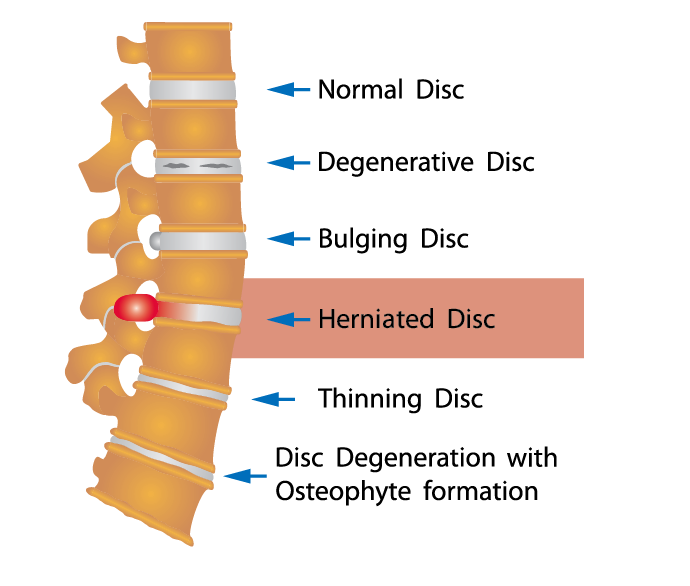

What are the different types of disc problems? | QI Spine

Bulging and Herniated Discs – Explained | Physical Health Care

What is the difference between a bulging disc and a herniated disc?